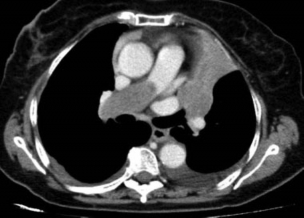

Presentamos el caso de una mujer de 72 años con antecedentes de carcinoma ductal infiltrante de mama en remisión seis años antes, que acudió a urgencias por dolor torácico, disnea y tos seca persistente. Tenía una angiografía coronaria reciente normal y los análisis de laboratorio revelaron como valor destacable un dímero-D de 742 µg/l. Con esos datos se solicitó desde el servicio de urgencias una angio-TC de arterias pulmonares (►Fig. 1) donde se apreciaba un voluminoso defecto de repleción en la arteria pulmonar derecha que se diagnosticó como TEP. La paciente fue anticoagulada y controlada con mejoría inicial, pero cuatro meses después volvió a urgencias con empeoramiento de la disnea, tos y hemoptisis. En las radiografías de tórax (►Fig. 2) se apreciaba un aumento de tamaño de arterias pulmonares con una masa parahiliar izquierda y atelectasia completa de lóbulo superior izquierdo (LSI), mejor valorados en la angio-TC torácica (►Fig. 3), donde persistía la ocupación arterial con unas características que, unidas a su evolución, sugirieron un origen tumoral. Se realizó biopsia a través de broncoscopia de la masa que obstruía el bronquio del lóbulo superior izquierdo, con un resultado histológico de sarcoma intimal de arterias pulmonares (►Fig. 4), patología muy poco frecuente y de difícil diagnóstico diferencial con el TEP.

TC torácica con contraste con ventana de mediastino donde se observa la persistencia de la ocupación de la arteria pulmonar derecha, con leve crecimiento respecto a la TC previa y con cierto grado de realce tras la administración del contraste yodado, por lo que se sugirió un origen tumoral. Además, se observa la masa que obstruye totalmente el bronquio del lóbulo superior izquierdo produciendo atelectasia completa, con la misma atenuación y realce que la masa que ocupa la arteria. Hay leve derrame pleural bilateral tal y como se apreciaba en la radiografía.